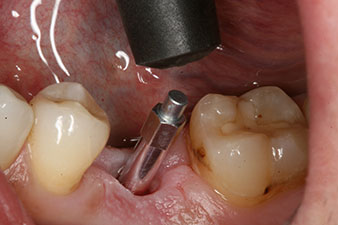

measuring probe

Fig. 6: Ten weeks later the gingiva former, which was screwed in place after placement of the implant, can be removed. In the linguo-buccal direction the ISQ value was virtually unchanged at 63 (measuring probe in proximity at a distance of 2-3 mm).

The implant was uncovered two months later and a gingiva former was screwed in (no picture).